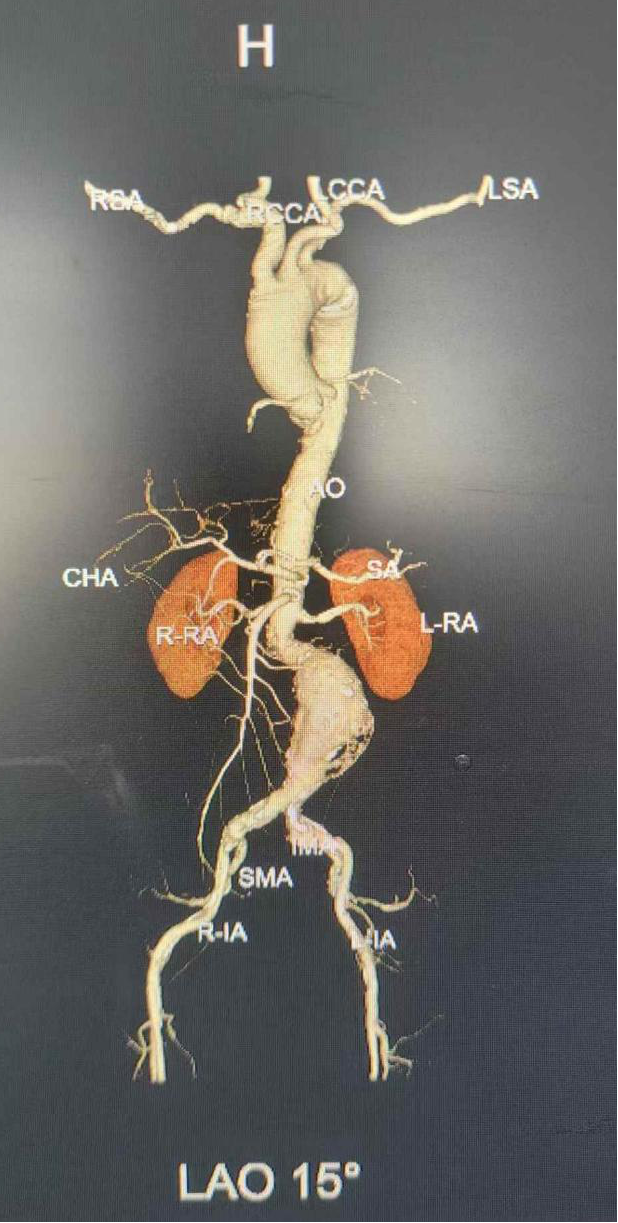

(術(shù)前CTA三維成像)

經(jīng)科室血管外科團隊詳細(xì)研判病情、術(shù)前MDT討論,并與患者家屬充分溝通,決定為患者實施“腹主動脈覆膜支架腔內(nèi)隔絕術(shù)”。普外一科(肝膽胰外科)血管外科團隊在中國科學(xué)技術(shù)大學(xué)附屬第一醫(yī)院血管外科專家指導(dǎo)下,與麻醉科、導(dǎo)管室等科室密切協(xié)作,術(shù)中采用股動脈穿刺入路,結(jié)合三維血管重建與數(shù)字減影血管造影(DSA)動態(tài)導(dǎo)航,成功完成腹主動脈-髂動脈覆膜支架置入術(shù)。

這場高難度的微創(chuàng)介入手術(shù)僅耗時1個小時便順利結(jié)束,術(shù)中造影顯示隔絕腹主動脈瘤的腹膜支架位置精準(zhǔn),成功保留了老人雙側(cè)腎動脈及髂內(nèi)動脈,最大程度保障了重要臟器的血流供應(yīng)和生理功能。在科室醫(yī)護團隊精心照護下,患者術(shù)后第5天康復(fù)出院。